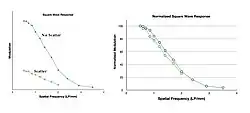

An amplitude profile through an image of the test object allows the modulation at each spatial frequency to be determined - see Figure 6.6 - and can be used to provide more complete information than the limiting resolution on its own.

Here, the modulation is obtained from the difference between the maximum and minimum pixel value at each spatial frequency and expressed in the form of a Square Wave Response (SWR) as shown in Figure 6.7. The modulation is seen to be relatively constant at low spatial frequencies and then to decrease rapidly towards zero. The SWR allows the spatial imaging capabilities to be expressed for both broad, relatively uniform objects, i.e. those with low spatial frequencies, and fine detail, i.e. those with high spatial frequencies, as well as features with intermediate frequencies.

In the presence of scatter, we can expect the reduction in contrast to give rise to reduced modulation at all spatial frequencies and a reduced ability to discriminate fine detail. This is illustrated in Figure 6.13 where modulation reduction is quite evident.

The impact on the square wave response is shown in Figure 6.14. It can be seen that scatter reduces the amplitude of the SWR and eliminates the modulation at frequencies above 2 LP/mm, in this case, so that they can no longer be resolved.

Note that a large reduction in modulation at very low spatial frequencies can be inferred from the figure. This phenomenon is generally referred to as the Low Frequency Drop and could conceivably be used as an indicator of scatter (and veiling glare) levels.